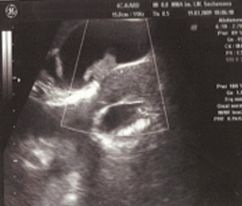

Больной О., 48 лет. Страдает БК в течение 13 лет. БК с поражением подвздошной кишки диагностирована 10 лет назад. До 2001 г. проводилась консервативная терапия. В 2004 г. в связи с развитием осложнений (образование инфильтрата и межкишечных свищей) была выполнена правосторонняя гемиколэктомия с резекцией 70 см подвздошной кишки и ограниченная левосторонняя гемиколэктомия. В 2006 г. — рецидив БК с участком поражения проксимальнее анастомоза. Изменений желчевыводящих путей не отмечалось. В 2007 г. в связи с развитием тонкокишечной непроходимости была выполнена резекция еще двух участков тонкой кишки. Через один год после второй операции при контрольном обследовании были выявлены изменения в желчном пузыре (рис. 4) — холестероз желчного пузыря (сетчато-полипозная форма).

Проводилось длительное лечение препаратами урсодезоксихолевой кислоты (Урсофальк) в дозе 15 мг/кг в сутки. При контрольном обследовании отмечалась значительная положительная динамика, заключающаяся в исчезновении полипа и уменьшении признаков холестероза (рис. 5).